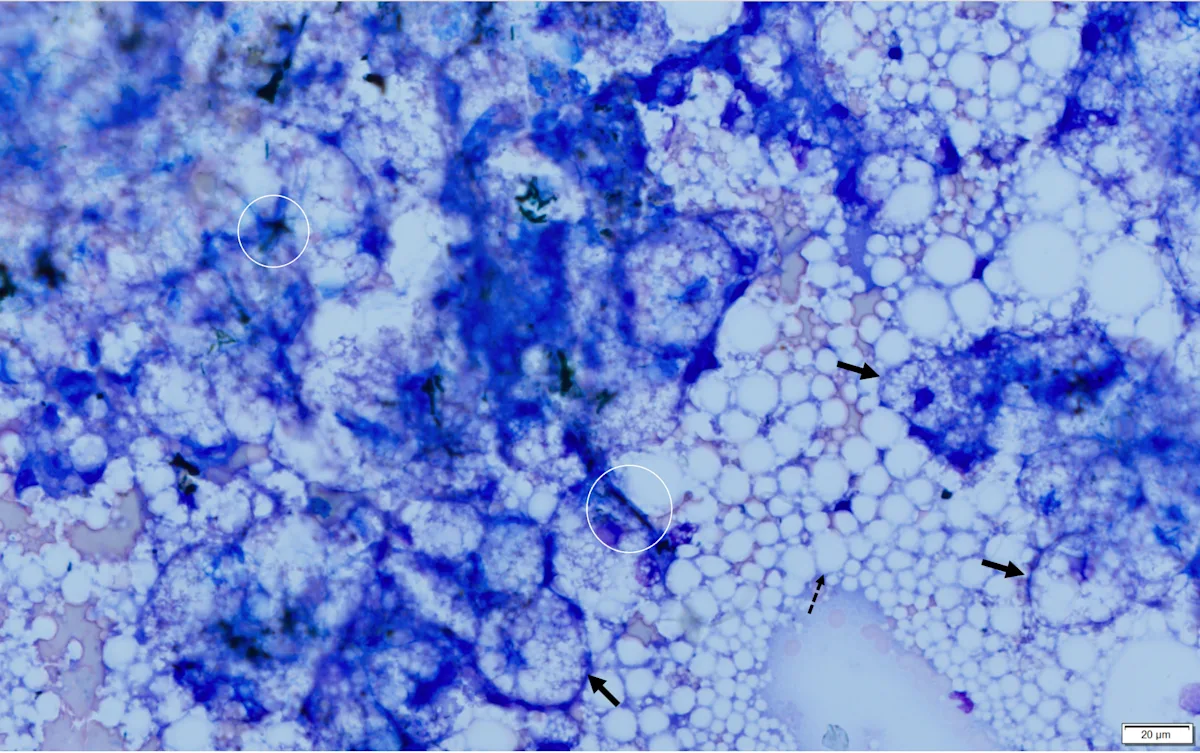

Abdominal ultrasonography revealed an enlarged liver with rounding of the caudal ventral margin. The hepatic parenchyma was hyperechoic and hyperattenuating, suggestive of lipid deposition. A fine-needle aspirate of the liver revealed abundant hepatocytes with marked vacuolation consistent with lipid (Figures 1 and 2).

Fine-needle aspirate from the liver of a cat. A cohesive sheet of hepatocytes (solid arrows) can be seen. Cytoplasm of hepatocytes is markedly distended with large (ie, macrovesicular) and small (ie, microvesicular) clear vacuoles that make observation of hepatocytes difficult. Darkly pigmented material (bile casts; circles) can be seen between cells, indicating cholestasis. Numerous free lipid droplets (dashed arrow) are also present in the background, but although this finding is typical with hepatic lipidosis, it is not diagnostic, as lipid must be within the cells. Modified Wright’s stain, 600× magnification